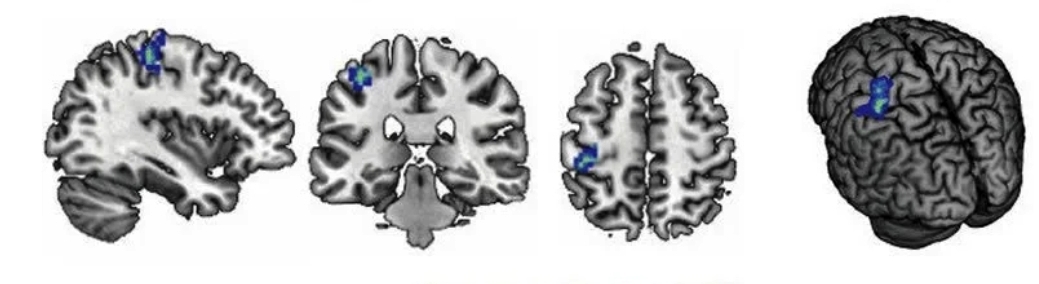

In recent years, my work has expanded toward more clinical applications, including developing and implementing intervention strategies to reduce anxiety, post-traumatic, and depressive symptoms, particularly in populations with social-communication challenges. Using brain stimulation techniques such as photobiomodulation and binaural beats, our aim is to alleviate different affective and cognitive symptoms.